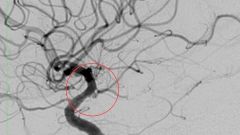

Столичные медики изучили анализы и поняли, что стандартный подход с трепанацией черепа не поможет. Аневризма расположилась в труднодоступном месте. После обсуждений на врачебном консилиуме специалисты решили провести эмболизацию – малоинвазивную и щадящую процедуру. Без вскрытия черепа женщина смогла бы быстро восстановиться и покинуть больничную палату уже через несколько дней после операции. Вскоре бригада хирургов приступила к процедуре. Вначале они установили во внутреннюю сонную артерию специальный катетер. «С его помощью по микропроводнику в полость аневризмы доставили микрокатетер, и еще один – в левую среднюю мозговую артерию. В терминальный отдел левой внутренней сонной артерии имплантировали стент с покрытием шейки аневризмы, после чего в ее полость была уложена особая микроспираль, благодаря которой врачам удалось восстановить нормальное состояние артерии и предотвратить разрыв», – говорится в сообщении Департамента здравоохранения Москвы.